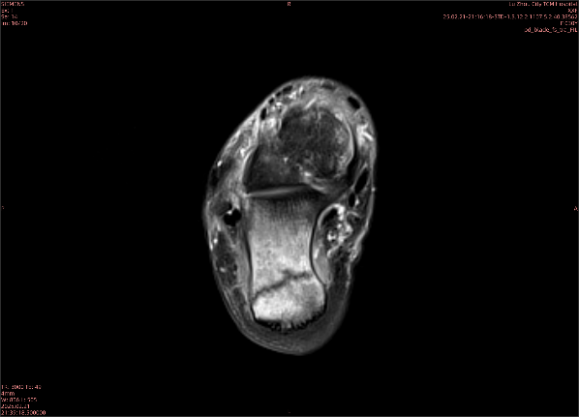

隱性骨折在MRI表現(xiàn)為T1WI序列上見由關(guān)節(jié)面向骨干走行的形態(tài)各異低信號區(qū),有線狀、條狀、紊亂低信號,信號強(qiáng)度不均勻。與T1WI低信號改變相對應(yīng)部位在T2WI上表現(xiàn)為相應(yīng)形狀的高、低混雜信號,且部分低信號周圍可見高信號水腫改變。STIR序列圖像上病灶呈顯著高信號,與信號被抑制的臨近正常骨髓形成鮮明對比,分界也較T2WI成像更為清楚。脂肪組織抑制技術(shù)是MRI的一個(gè)重要性能,脂肪抑制技術(shù)在MRI應(yīng)用中可以改善組織對比和增加病變顯示機(jī)會,這樣骨髓的脂肪抑制后就不會有任何信號,而隱性骨折線及骨髓水腫的異常高信號就會更加明顯的顯示出來。

舉例圖像

圖2

專業(yè)解釋看不懂沒關(guān)系,大家看圖1和圖2就可以了,這是同一個(gè)患者跟骨的磁共振和CT圖像,圖1的紅色箭頭指示的黑線就是磁共振圖像顯示的骨折線,一目了然。而對比圖2的CT圖像上并未顯示異常。